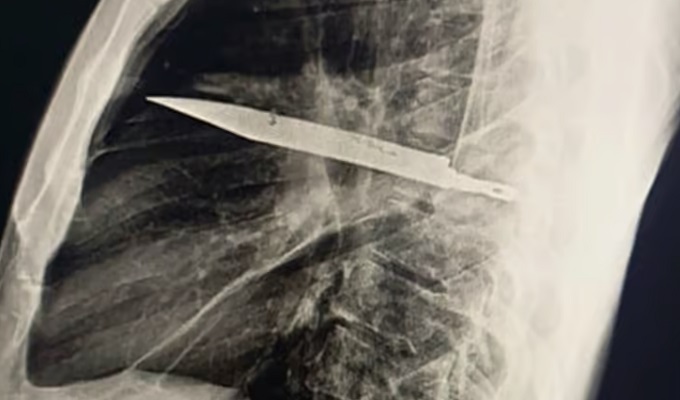

Hombre vivió ocho años con una hoja de cuchillo incrustada en el pecho sin saberlo

El objeto fue hallado tras una radiografía. Pese a la gravedad del caso, la cirugía para extraerlo fue exitosa y el paciente se recuperó sin complicaciones.

Un insólito caso sorprendió a médicos en Tanzania. Un hombre de 44 años acudió al hospital luego de notar pus en uno de sus pezones, sin imaginar que la causa era una hoja de cuchillo de ocho centímetros alojada en su cavidad torácica.

De acuerdo con un estudio publicado por la National Library of Medicine, el paciente relató que había sufrido una violenta pelea ocho años atrás, donde probablemente resultó herido. Sin embargo, en ese momento no se le realizaron radiografías debido a la falta de recursos y las heridas cicatrizaron, ocultando la presencia del objeto.

Al realizarle una radiografía reciente, los especialistas detectaron la hoja incrustada debajo del hombro derecho. A pesar de ello, el hombre nunca presentó dificultad para respirar, fiebre ni dolor torácico. Los médicos explicaron que el tejido muerto rodeó al objeto, lo que provocó la secreción de pus al exterior.

La cirugía para extraer la hoja fue exitosa y el paciente se recuperó sin mayores complicaciones, aunque durante la intervención se identificó un defecto en el pulmón derecho.

Los especialistas calificaron el caso como extremadamente raro, ya que normalmente este tipo de lesiones son detectadas poco tiempo después de ocurridas.